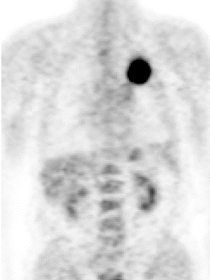

Рис. 3. Позитронная эмиссионная томография пациента О., 72 лет с большой периферической опухолью верхней доли правого легкого. При биопсии - плоскоклеточный рак. При видеомедиастиноскопии - метастазов в лимфоузлах средостения не выявлено. В апреле 2007 года пациент успешно прооперирован в нашем Центре в объеме расширенной верхней лобэктомии справа. При контрольном осмотре в 2013 году состояние больного удовлетворительное признаков, рецидива опухоли нет.

В нашем Центре используются современные малоинвазивные способы биопсии, которые позволяют установить диагноз как при опухолях крупных бронхов (центральный рак), так и при опухолях расположенных в периферических участках легкого. Основную роль в биопсии опухолей легких играет фибробронхоскопия, в том числе чрезбронхиальная (рис. 4, рис.5). Иногда приходится прибегать к различным способам чрезкожной игловой биопсии. В редких случаях ни один из современных методов диагностики не позволяет подобраться к неудобно расположенной опухоли. В таких ситуациях после полного обследования (включая КТ, ПЭТ, фибробронхоскопию) биопсия опухоли выполняется уже во время лечебно-диагностической операции.